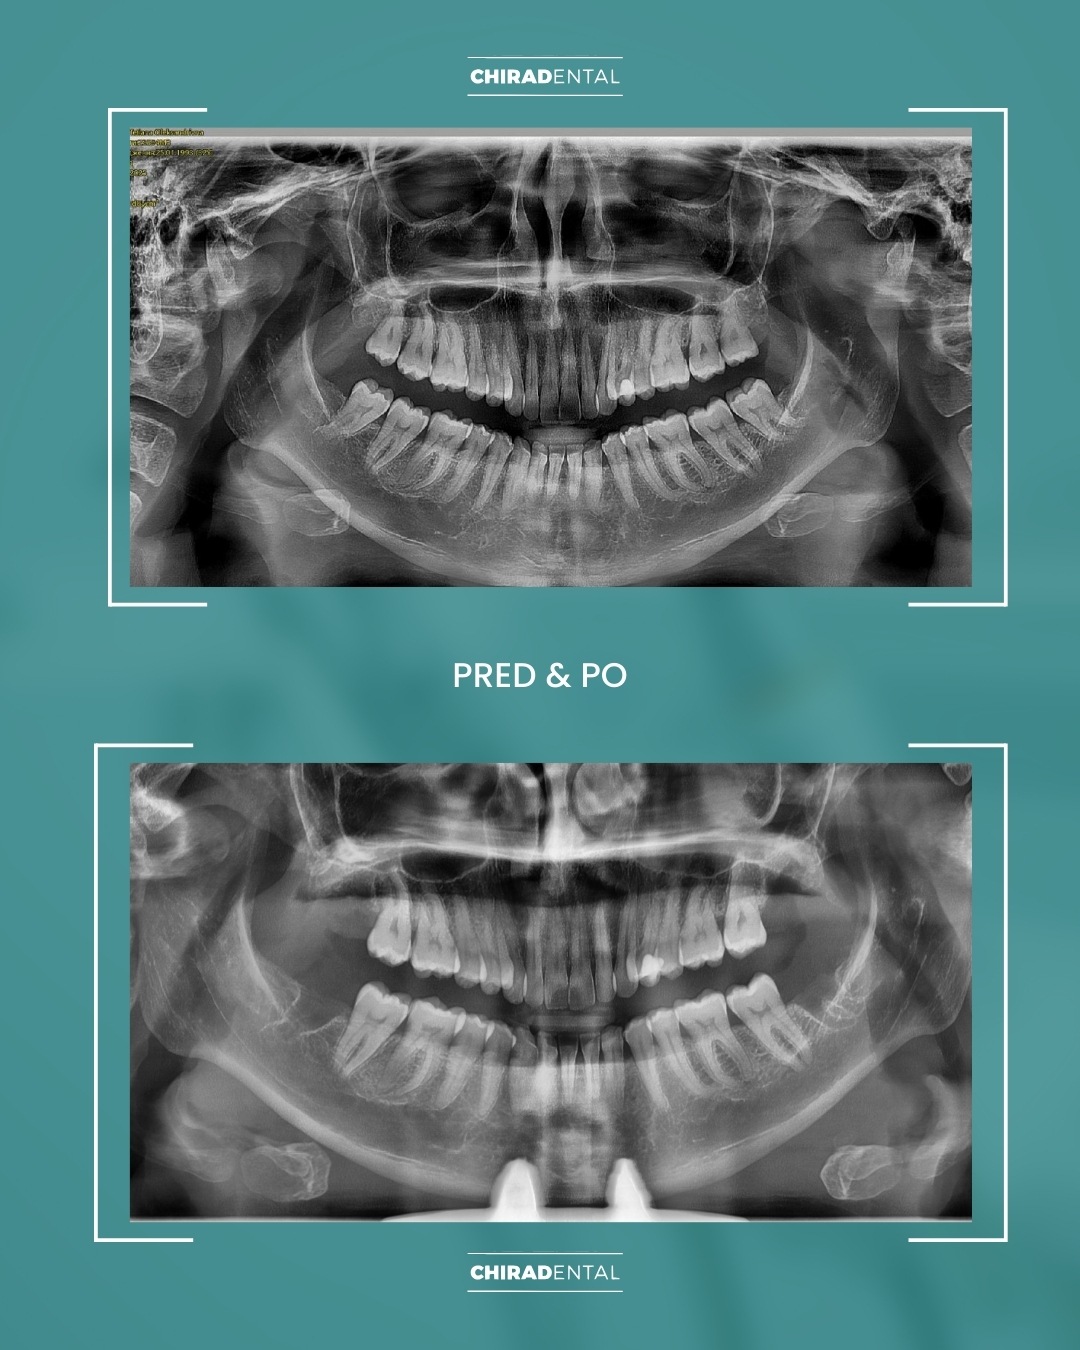

Prineste si so sebou všetky dostupné röntgenové snímky, modely čeľustí a pod.

Ak tieto informacie nemáte, nevadí. Počas konzultácie vykonáme všetky potrebné vyšetrenia – rádiologické vyšetrenie ortopantomogram (skr. OPG) röntgenový snímok alebo 3D snímka CT (CBCT), odtlačky (3D sken) čeľustí, fotografovanie a videodokumentáciu chrupu, čeľustí, úsmevu, tváre a ďalšie diagnostické úkony. Na základe získaných údajov budete môcť absolvovať primárnu konzultáciu s naším špecialistom